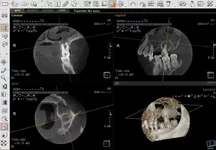

Хотя увы прошло 6 лет и имею рецедив там где зуб сохранили, опять киста и еще одна тоже в процессе образования, просто ппц блин вроде снимки показывают что качественно каналы запломбированы, толи материал херовый был толи особенность такая анатомическая.

челюстно лицевая хирургия не работает с искуственной костью, а засыпка костю вроде бы дело разумное, кстати как делают операцию с засыпкой костью можно посмотреть на ютубе только это не для слабонервных